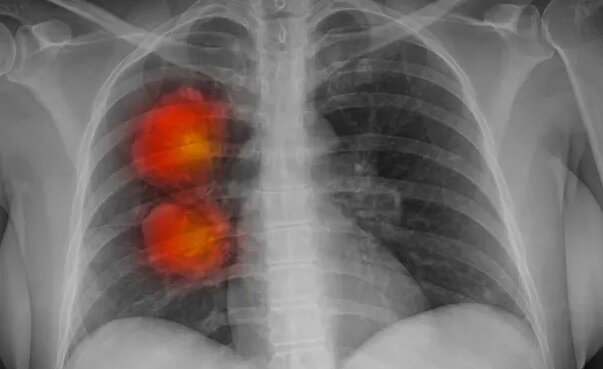

به گزارش ایسنا، بر اساس نتایج مطالعه متخصصان آمریکایی، استعمال سیگار، مصرف مواد الکلی، اضافه وزن و سایر عوامل خطرزا عامل تقریبا نیمی از مرگ و میرهای ناشی از سرطان در سراسر جهان هستند.

اکنون گروهی از متخصصان آمریکایی چگونگی تاثیر عوامل خطر در مرگ و میر ناشی از سرطان را در سطح جهان بررسی کردند. استعمال دخانیات، مصرف مواد الکلی و شاخص توده بدنی بالا (BMI) بزرگترین عوامل موثر در این موضوع هستند. در مجموع، عوامل خطرزا عامل تقریبا ۴.۴۵ میلیون مرگ ناشی از سرطان در سال هستند.

به گفته متخصصان، این آمار نشان دهنده ۴۴.۴ درصد از کل مرگ و میر ناشی از سرطان در سراسر جهان است. نیمی از مرگ و میرهای ناشی از سرطان در میان مردان در سال ۲۰۱۹ به دلیل عوامل خطرزا بوده و در زنان بیش از یک سوم مجموع مرگ و میرهای ناشی از سرطان تحت تاثیر این عوامل بوده است.